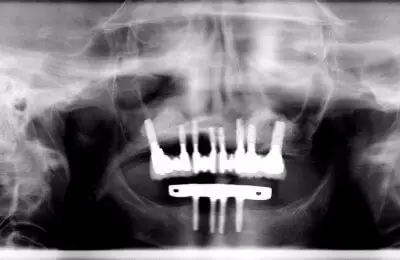

Full Arch Treatment Case Study

Full Arch Treatment-Case Study